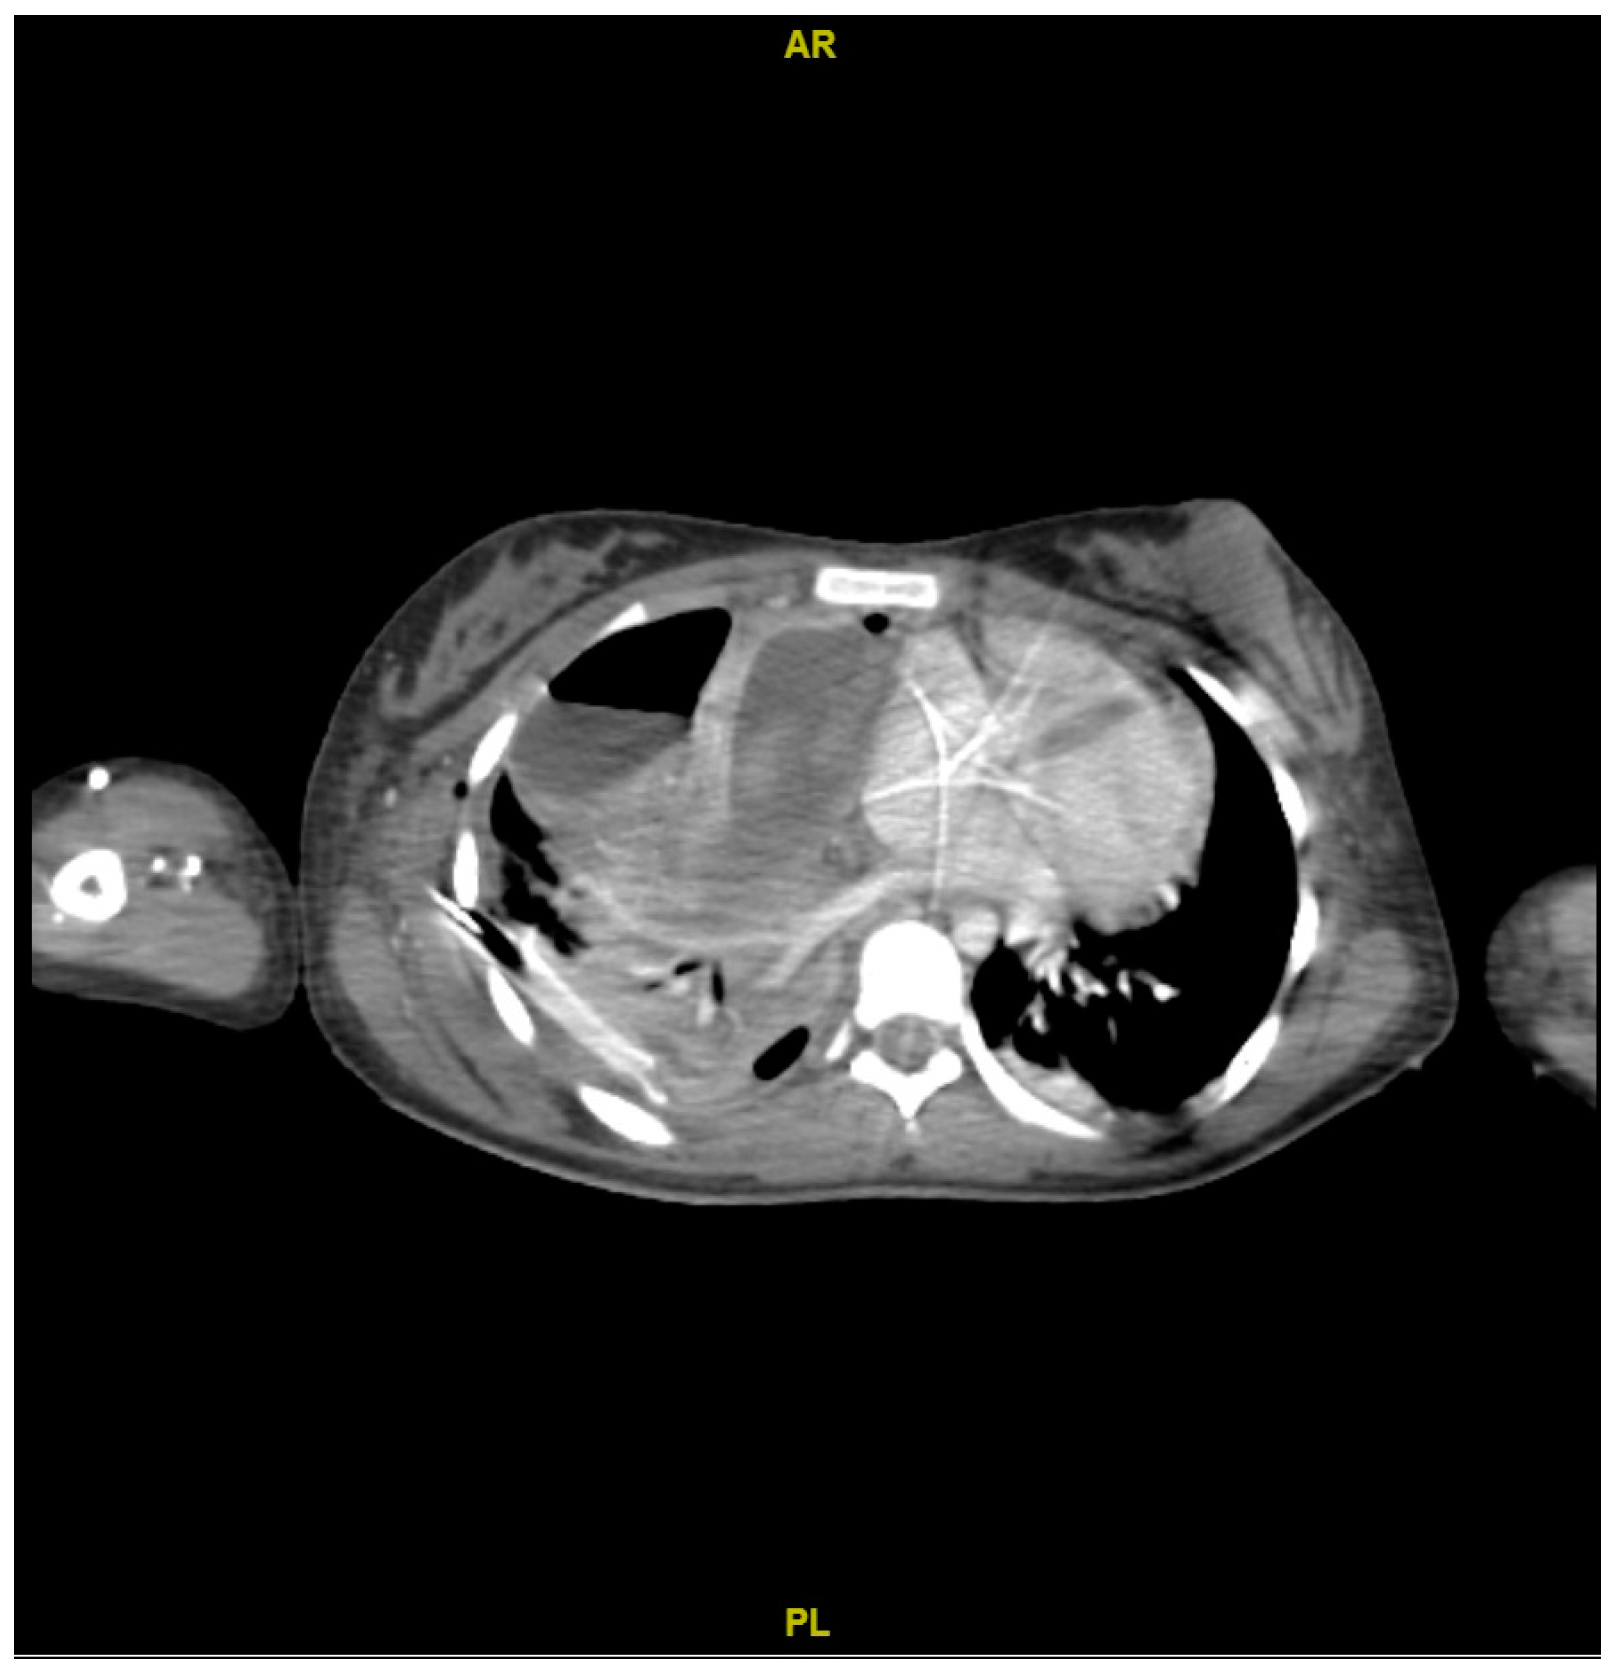

Therefore, the cardiothoracic surgery service re-evaluated the patient. Surgical lavage was performed to remove the pleural drainage, and a white sponge and a silver sponge with a seal were placed. The VAC system was used, opting for conservative management due to the high risk of developing a bronchopleural fistula (Figure 5).

Figure 5. Computed tomography (CT) scan shows subcutaneous emphysema due to gas in soft tissues on the rib cage, with thickening and abscessified collection.